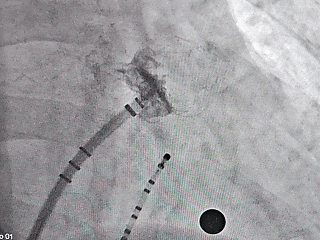

Lefort封堵器释放

Lefort封堵器评估符合PASS原则,释放封堵器,封堵器位置稳定且未见残余漏,封堵完美。

符合PASS释放原则,封堵形态完美